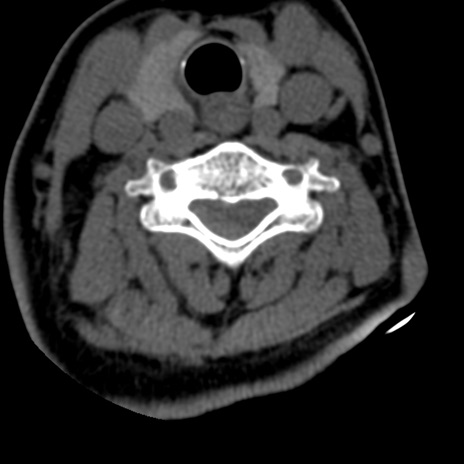

症例50 頚椎CT(横断像)

矢状断像